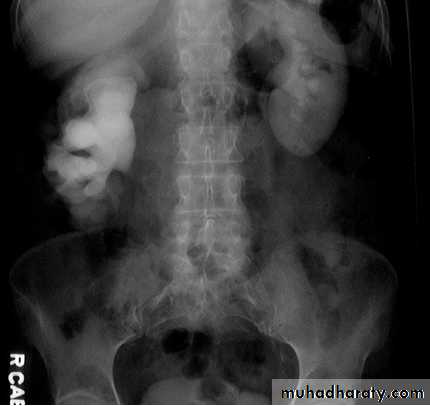

IVU excretory phase showing marked dilated PCS , but normal ureter …

DX congenital PUJ obstruction.Renal masses